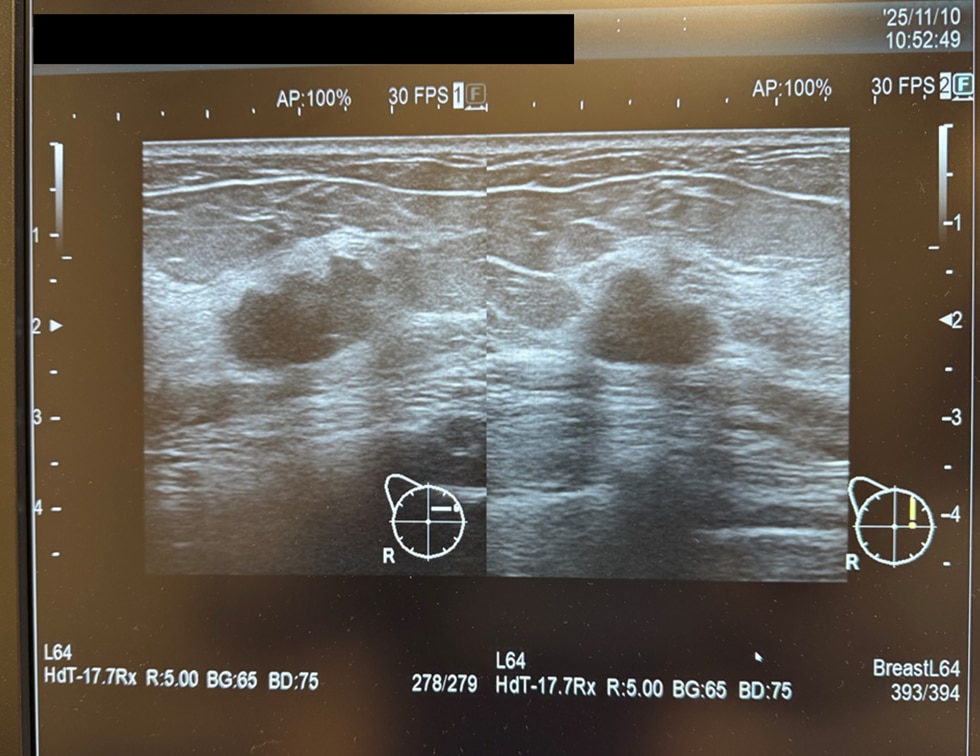

実は、診断を受けた時点でも、自分で触れて分かるしこりはありませんでした。もしSYMGRAMを受けていなければ、自覚症状が出るまで放置し、発見がもっと遅れていたはずです。実際に、11月から12月の1ヶ月のうちに、1.8センチから2.1センチへとあっという間に大きくなりました。11月のタイミングで受診できたことは、まさに不幸中の幸いでした。

▲モニターに映し出されたエコー画像